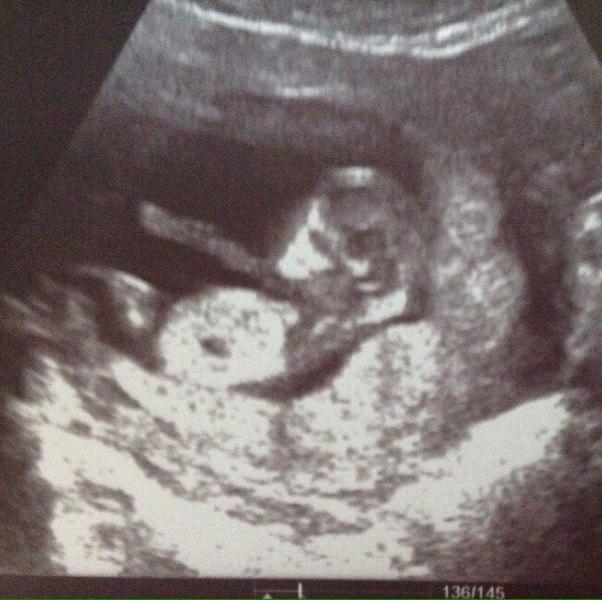

Сегодня у нас 39 недель, а зарегистрировалась я в preggie когда моя малышка была маленькой вишенкой и нам было всего 9 недель! Сегодня мы уже по мнению прегги - арбузик! Ягодка моя, осталась ягодкой 😄

2ого марта, на приёме мне сказали, что моя девочка не досидит до 16ого числа, но приём назначили - мало ли! Шах и мат от моей дочуры этим врачам! Как раз пока сижу в очереди на приём, вспомню все фишечки своей беременности!)

Пролетело время конечно невероятно быстро, до 20 недель и даже больше, я с...